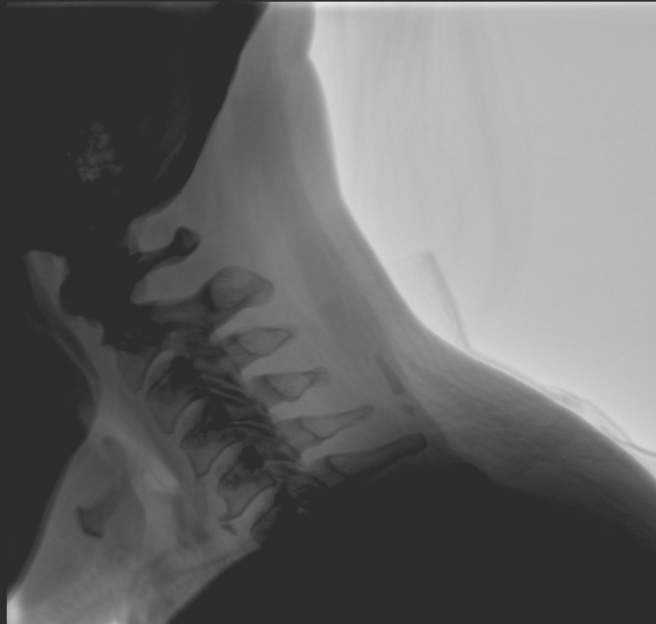

臨床應用廣泛,適用于關節(jié)手術、創(chuàng)傷手術、脊柱手術、疼痛治療等。

平板尺寸升級 呈現(xiàn)更多解剖細節(jié)

采用30CM×30CM大尺寸動態(tài)平板探測器,成像面積較傳統(tǒng)平板探測器大幅提升。

圖像清晰細膩

高清像素,低信噪比,細小的組織結構也可以清晰顯示。

Clinical picture

臨床圖片